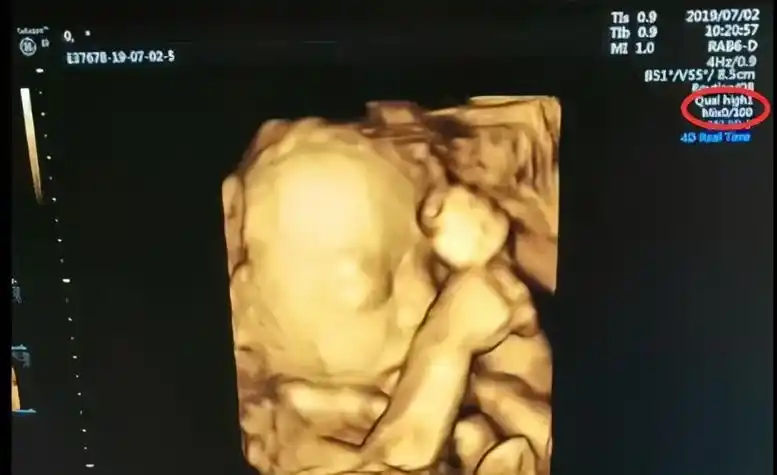

四维彩超,两次发现貌似蛋蛋的两个对称的东西,中间间隔几分钟,再看

四维顺利通过照到明显小jj 男宝果然好调皮 附症状

(女宝腿部间性别特征)但四维彩超的主要目的并非是看胎儿性别,当然

区别图一般来说,怀孕到了四个月的时候,胎儿的生殖器官已经开始发育了

四维彩超看男女这么简单, 学到了